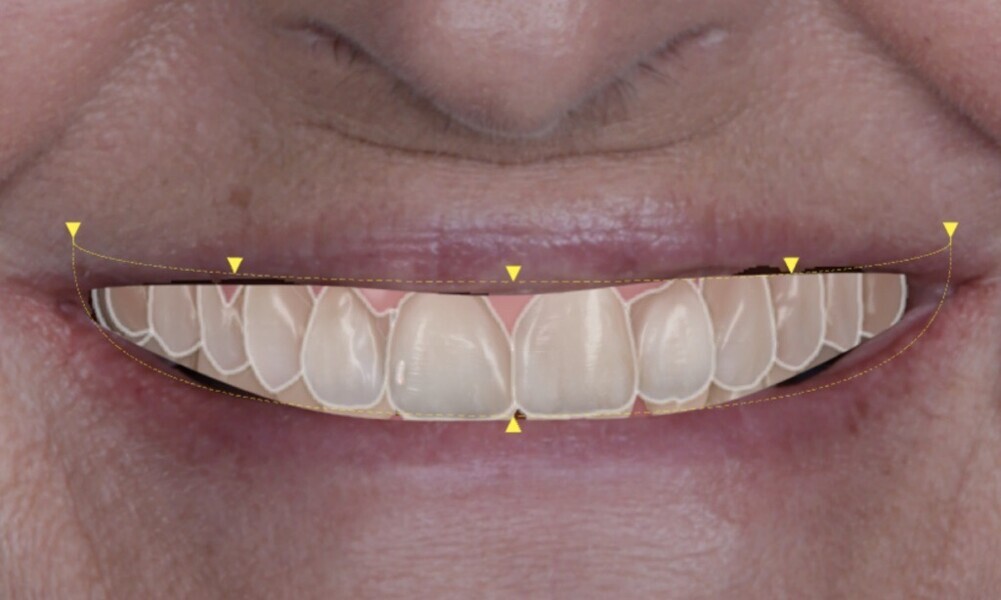

To ensure precise and predictable treatment planning, the DICOM files, STL files and clinical photographs were seamlessly integrated into Smilecloud, utilising advanced artificial intelligence technologies to deliver a highly personalised smile with exceptional precision (Figs. 11–15).

Figs. 11–15: DICOM files, STL files and clinical photographs were integrated into Smilecloud, leveraging artificial intelligence for precise, personalised smile design.